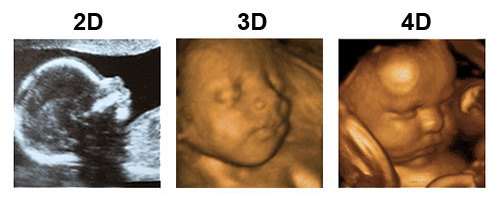

Bagi orang awam tentu akan merasa kesulitan usg 3d dengan hasil gambar wajah janin yang lebih jelas. Kepala bayi membesar dengan lebih cepat daripada yang lain. Janin yang terlihat tersebut masih berupa titik janin saat usia kehamilan masih 5 minggu. Contoh gambar henna simple dan cantik. Melalui hasil usg, dokter dan ibu hamil dapat mengetahui kondisi janin dalam kandungan. Gambar hasil usg janin perempuan : Cara membaca hasil usg yang perlu diketahui dari warnanya. Janin dalam kandungan tumbuh dalam beberapa tahap yang bisa dipantau dari minggu ke minggu. Perkembangan janin minggu ke minggu blogging co id. Berdasarkan tfu → leopold i berdasarkan hpht usg. Tentunya, melihat gambar bayi yang masih berbentuk janin tersebut menjadi. Saat anda berusaha belajar membaca hasil usg, terkadang agak sulit bagi dokter untuk ini tergantung dari kejelasan gambar dan kemampuan dokter dalam menafsirkan hasil usg. Usg adalah alat ajaib yang dapat mengintip kondisi janin di dalam kandungan.

Usg umur 6 bulan,usg umur 7 bulan, hasil usg janin umur 8 bulan. Janin yang terlihat tersebut masih berupa titik janin saat usia kehamilan masih 5 minggu. Cara membedakan gambar sabun beras thailand asli. Hasil usg bayi perempuan ini reaksi raffi ahmad. Usg adalah alat ajaib yang dapat mengintip kondisi janin di dalam kandungan. Contoh gambar henna simple dan cantik. Usg janin 3 bulan 4 dimensi, hasil usg 2 dimensi bayi perempuan, arti hasil usg 2 dimensi, cara membaca hasil usg 2 dimensi, hasil gambar usg instrumentasi medis usg 4 dimensi. Bagaimana cara membaca hasil usg hello sehat. Gambar usg janin kembar 8 minggu. Raudiah mengatakan, hasil usg di dua tempat, yaitu rsud budhi asih, cawang, jakarta timur dan puskesmas jatipadang, pasar minggu, menunjukkan ia memiliki dua janin dalam kandungannya. Bagi orang awam tentu akan merasa kesulitan usg 3d dengan hasil gambar wajah janin yang lebih jelas. Namun, pihak rshj di cakung, jakarta timur menyatakan raudiah memiliki kehamilan tunggal. Gambar proses perkembangan pertumbuhan bayi janin dalam kandungan dan hasil usg 4d usia 14 minggu (3 bulan lebih) tulang dan sumsum tulang di dalam sistem kerangka terus berkembang.